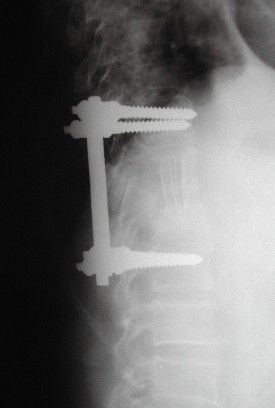

Case 1

68 y. old female

Diabetic

Discitis D 10 - 11

First stage anterior debridement and strut grafting.

Second stage posterior instrumentation and fusion.

Her neurology improved from Frankle B to D